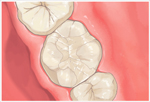

アメリカのヒューストン発のDoc's Best Cements(ドックベストセメントまたはドックスベストセメント)により痛くない、削らない、神経を取らない治療が可能になりました。(従来の保険治療で行うような予防的な拡大処置としてむし歯以外の健全な歯質を削らないということです。

まったく歯を削らないという意味ではありません。) ドックベストセメントは、Dr.Fraserが1990年に開発したミネラルを含んだ銅セメントです。

ドッグベストセメント治療は、銅、酸化亜鉛、酸化チタン、リン酸、水酸化アルミなどを主成分とする素材を使います。鉄(Fe)イオンと銅(Cu)イオンのコンビネーションによる殺菌力が、むし歯に効果的に作用することで、むし歯菌に侵された歯の象牙質の無菌化を促すという大きな働きがあります。

メリット一般的なむし歯治療と違い、ドッグベストセメント治療は必要以上に歯を削らないで済みますので、歯を削る違和感もなく、痛みを感じないので、麻酔注射も必要ない場合がほとんどです。

ドッグベストセメントの鉄(Fe)イオンと銅(Cu)イオンのコンビネーションによる殺菌力で患部を殺菌することで、神経を残せる可能性が高くなります。

むし歯菌に侵されている歯の内部の象牙質をドッグベストセメントの鉄(Fe)イオンと銅(Cu)イオンで殺菌することで、歯の象牙質部分の再石灰化を促します。